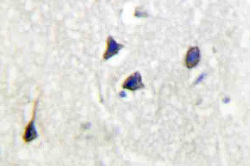

AP20397PU-N IHC

Full details

Method:

Immunohistochemistry